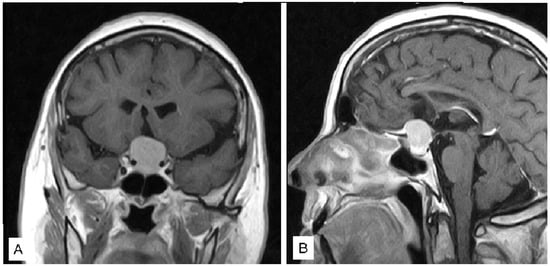

3.1.1. Case 1

3.1.2. Case 2

3.1.3. Case 3